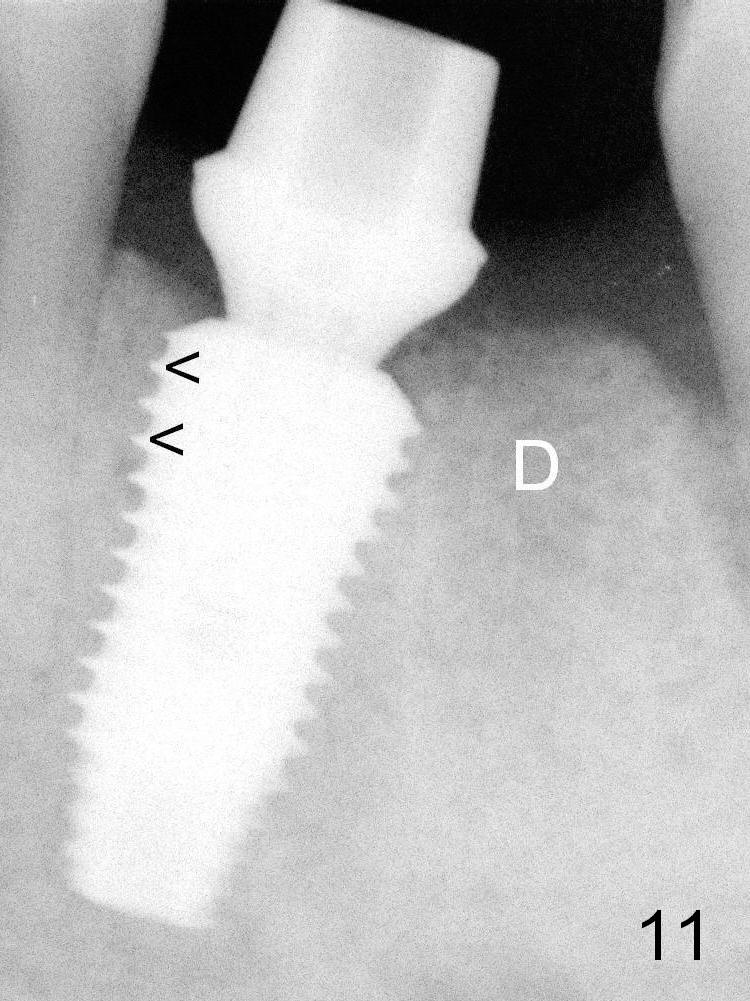

Four months postop, the bone density in the original mesial (Fig.11 <) and distal (D) sockets increases, suggesting osteointegration.